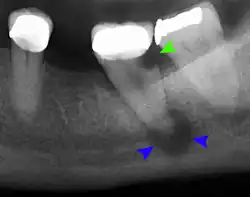

Once a person is having symptoms related to Gigantiform cementoma it is suggest to seek medical attention. The health providers that can help would be a Dentist, Oral Surgeon, Oral Pathologist, and Prosthodontist. A dentist can do an exam and take x-rays to evaluate symptoms and to be able to refer the patient to the correct specialist. An Oral Surgeon are specialized with surgical procedures related to the mouth, jaw and the face. An Oral Pathologist is able to help with diagnosis by examining the tissues samples in order to diagnosis and treat diseases related the jaw, and mouth. Prosthodontist are able to aid with the missing teeth. The doctors specialize with dental prosthetics. In order to diagnosis a patient with Gigantiform cementom there has to be X-ray done that provides the doctor with the view of the jaw and the teeth to identify the tumor and to also be able to see the size of the tumor. There are different types of X-rays that can be done which are the Panoramic Radiograph and Cone Beam Computed Tomography (CBCT). Biopsy may be suggested by an Oral Surgeon to be able to collect tissues from the tumor to get samples for histological examine, this is necessary to confirm diagnosis. Blood test can also be done to confirm diagnosis.